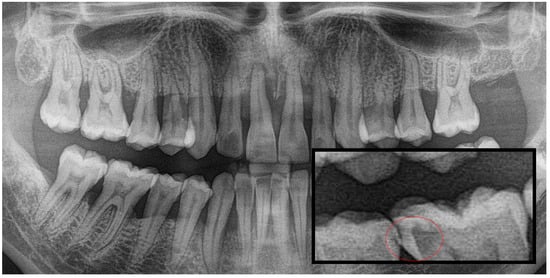

Figure 2.

Panoramic radiography and segmented occlusal caries, red circle shows the caries.